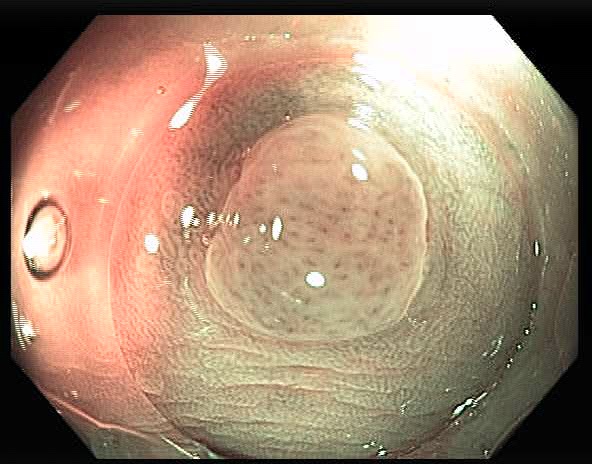

In our previous work [6], we have collected and annotated a collection of endoscopic dataset, which contains 157 video sequences and a total of 35,981 frames. We have also labeled the ground truth of the polyp location and histogram class. In order to evaluate the performance of different classification models, we generate two polyp datasets from the annotated endoscopic dataset. As shown in Fig 2, one dataset (set-1) only contains the cropped polyp patches from the original video frames; the other dataset (set-2) contains not only the cropped polyps but also around 55% background around the polyps. As described in [8], polyps have different surrounding and vascular patterns and color in vessels and background according to the type of polyps. Therefore, we generate set-2 to study the effect of background features [8] in polyp classification.

Fig 2 illustrates the difference between the two generated datasets. We have evaluated and compared the performance of six classification models on these two datasets. Our results show that there is no significant difference in classification accuracy between the two datasets. We have also analyzed the performance based on both individual frames and individual sequences. The major contribution of this work include:

For the labeled dataset, we randomly split all the videos into training, validation, and test sets which contains 119, 16, and 22 video sequences, respectively. The study focuses on evaluating the performance of the state-of-the-art classification models. We assume the polyps have been accurately detected and generate two separate datasets for the evaluation. As shown in Fig 2, set-1 only contains the patches of the cropped polyps, and set-2 contains not only the cropped polyps but also about 55% background around the polyps.